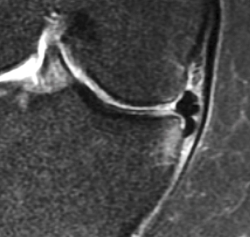

Figura 5. Fragmento del menisco interno subluxado en la gotera tibial con pinzamiento óseo. Este tipo de lesión degenerativa específica del menisco podría dar lugar a importantes síntomas mecánicos y dolor.